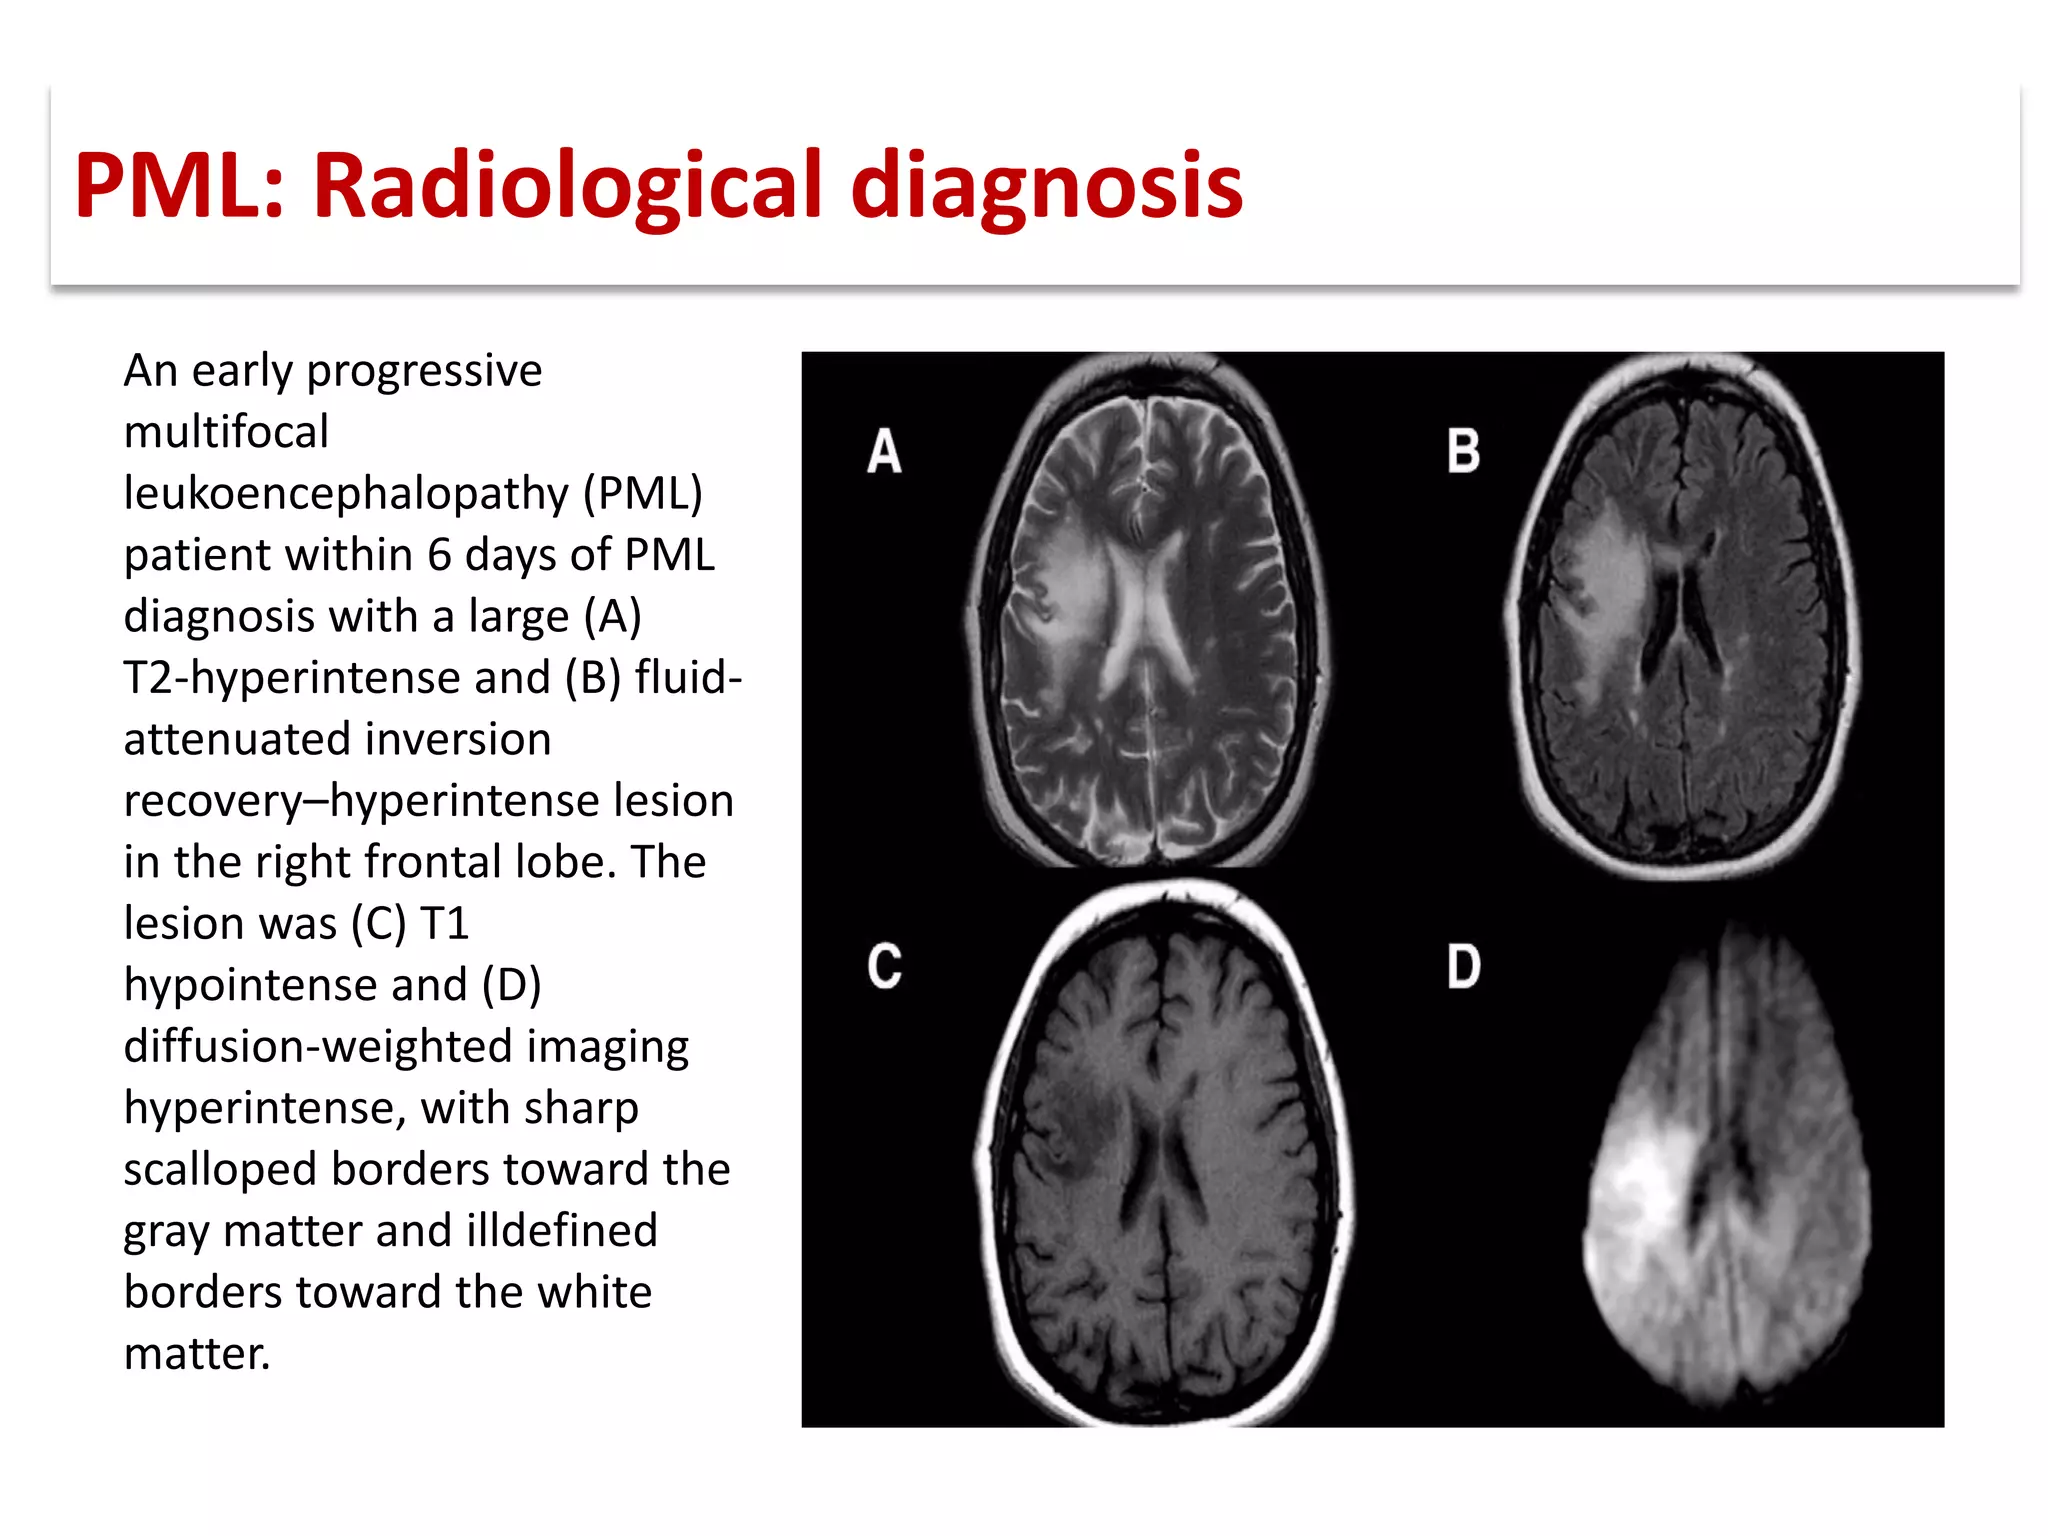

This document discusses progressive multifocal leukoencephalopathy (PML), an opportunistic infection caused by the John Cunningham virus (JCV) that leads to demyelination in the central nervous system. It highlights the epidemiology, clinical manifestations, diagnostic methods, and risk factors associated with PML, particularly in immunocompromised patients and those undergoing immunomodulatory therapies. It also presents data on the incidence of PML in patients treated with natalizumab and other therapies, addressing the relationships between these treatments and the development of PML.